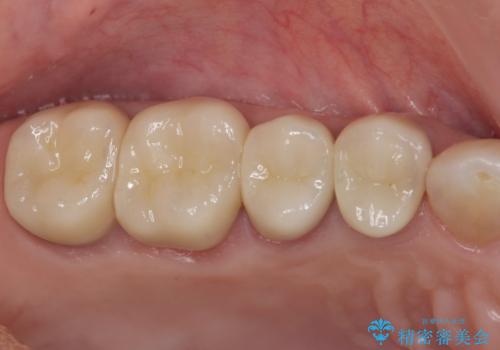

臼歯部メタルフリー再補綴

- 110万円(仮歯×8・ファイバーコア×6・ジルコニアクラウン×8)費用は治療当時の料金となります

装着して長期間経過したブリッジやクラウンは隙間から細菌が侵入し虫歯が再発してしまっていることがあります。

長期的に問題のないブリッジ・クラウンを作製するため、虫歯をしっかりと除去すること精密な根管治療を行うことが肝要です。